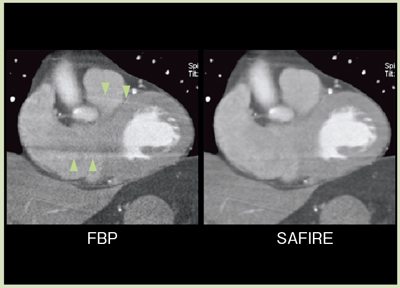

サイノグラムベースの反復処理によるアーチファクト抑制効果を図6に示す。椎体からのストリーク状のアーチファクトや,周辺のモアレ状のアーチファクトが,SAFIREによって効果的に抑制されていることがわかる。この効果は,例えば心臓CTの臨床例においても観察することができる(図7)。

![]() 図6 FBPとSAFIREのアーチファクト抑制効果の比較 |

![]() 図7 臨床例によるFBPとSAFIREのアーチファクト抑制効果の比較 |